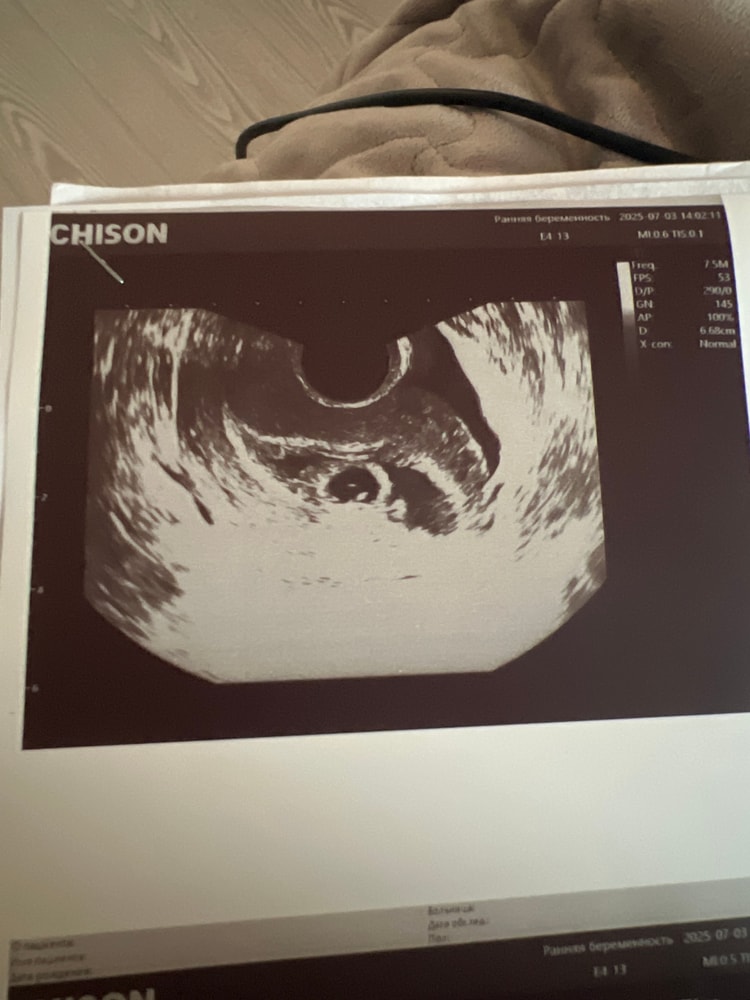

Пошла на УЗИ. Было интересно что за второе черное пятно на предыдущем узи. В итоге, это ретрохориальная гематома размером 25,8*15,8 мм. Я в шоке! Жду планового приема у ре 10 числа. Но не кровит, не болит. Все в норме

Зато, КТР 2,5 мм, СВД 13,7 мм, имеется сердцебиение ( его прям видно, так интересно колышется), жм 2,6 мм и свое желтое тело. Срок по узи 5,5 недель